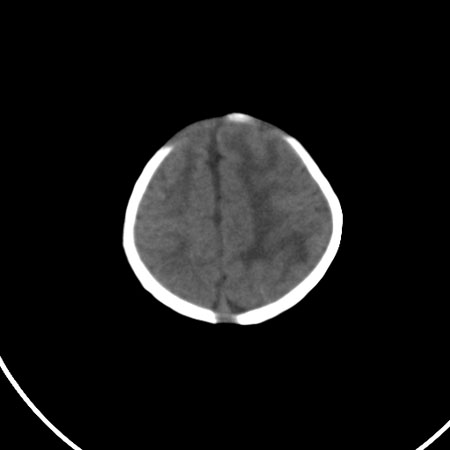

以下是引用小初学者在2009-1-10 17:51:00的发言:[br]考虑缺血缺氧性脑病后遗性改变。

以下是引用拾荒者在2009-1-10 19:23:00的发言:[br]生后有蛛网膜下腔出血病史,现幕上脑室明显扩张,脑室周围白质局限性密度减低,考虑hie脑病后遗表现。